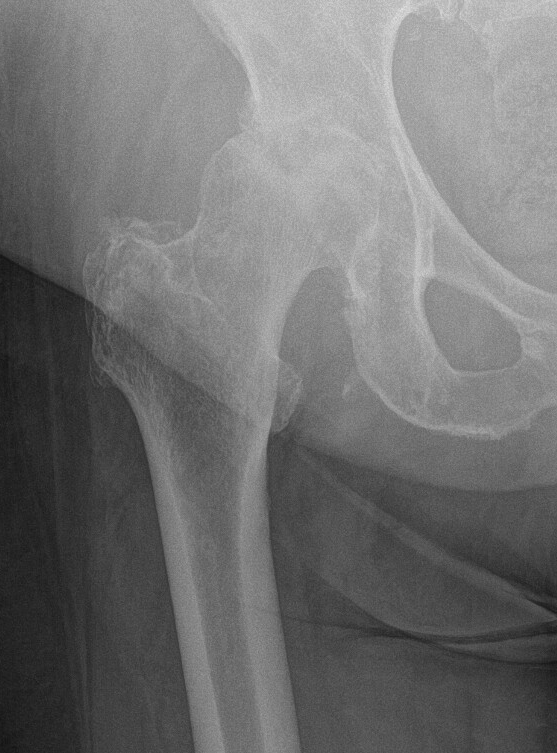

Pokročilá koxartróza (obr. 2) je zdaleka nejčastějším důvodem k implantaci TEP. Jedná se o onemocnění, na jehož vzniku se podílí více faktorů (věkem podmíněná degenerace, celkové opotřebení kloubu v průběhu času apod.). Existuje však rovněž tzv. sekundární artróza kyčle, která vzniká na podkladě určitého specifického primárního onemocnění (vývojová kyčelní dysplazie, Perthesovo onemocnění, stavy po zánětech, úrazech, operacích apod.) U kloubu postiženého artrózou postupně dochází k destrukci kloubní chrupavky a přilehlé kostní tkáně. Tyto změny můžeme hodnotit pomocí rentgenových (RTG) snímků, kde lze prokázat zúžení kloubní štěrbiny, tvorbu kostěných výrůstků (osteofytů) a v nejzazších fázích až nekrózu kostní tkáně.

Obr. 2 Obraz koxartrózy

Zúžení (až zánik) kloubní štěrbiny, tvorba osteofytů, kostní cysty.

Zdroj: Ortopedická klinika FZS UJEP a MNUL.